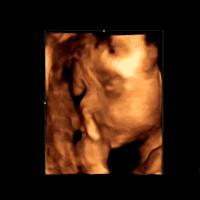

三维彩超和超声影像(四维彩超)的区别主要在于在一个“时间维”,也就是说,三维彩超是图片,是静态的,超声影像(四维彩超)是影像,是动态的,可以让孕妈妈看到胎儿一连串的动作。三维彩超只能是某个时间点上的照片,检查结果比较片面,超声影像(四维彩超)采用四维成像技术,检查结果更为直观,立体,并对目标对象进行连续多维扫描,可以刻录成光盘。

超声影像(四维彩超)是在三维彩超的基础上的一个技术提升,是一个动态的检查过程,仪器要更加先进,影像更加清晰。重要的是,超声影像(四维彩超)能够多方位、多角度地观察宫内胎儿的生长发育情况,为早期筛查胎儿先天性体表畸形和先天性心脏疾病提供准确的科学依据,而且动态记录宫内影像,也比较具有纪念性意义。